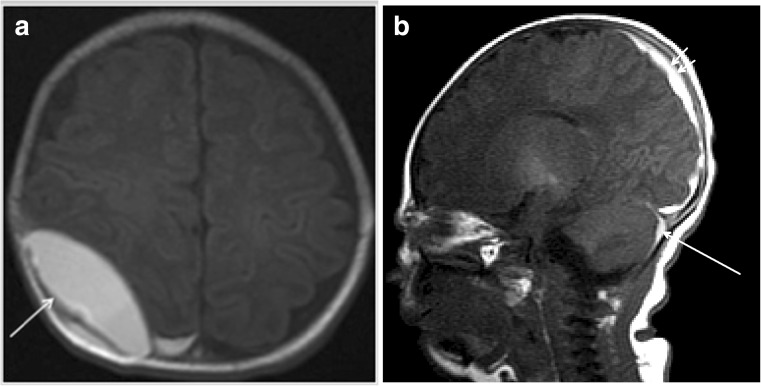

Fig. 2.

A 9-day-old female neonate exhibited both supratentorial and infratentorial SDH and EDH at the right parietal convexity. She was born via spontaneous vaginal delivery at 38 weeks weighing 3070 g. She presented with jaundice 4 days postnatally and exhibited a EDH (arrow) at the right parietal convexity on axial T1WI MR imaging and b SDH over both cerebellar and parietooccipital lobes (short arrows). She underwent burr hole drainage of EDH 11 days postnatally. She was followed in the clinic for 4 years and developed normally

SDH was the most common type of hemorrhage (40/42, 95.2%). Seven SAH, one EDH (Fig. 2), three GMH (Fig. 3), and nine intraparenchymal hemorrhages were identified. A total of 16 infants had two or more types of hemorrhage. SDH was commonly located along the tentorium (n = 38), over the cerebellar hemispheres (n = 39), along the interhemispheric fissure (n = 10), over the occipital lobes (n = 13), and parietooccipital lobes (n = 11). The frontal (n = 4), parietal (n = 3), and cerebellar (n = 2) lobes were most commonly involved in patients with intraparenchymal hemorrhage. A single lobe was involved in eight of nine infants with intraparenchymal hemorrhage. There was no significant correlation between the clinical outcome and site of hemorrhage. SDH was resolved or decreased in follow-up patients (9/42, 21.4%).